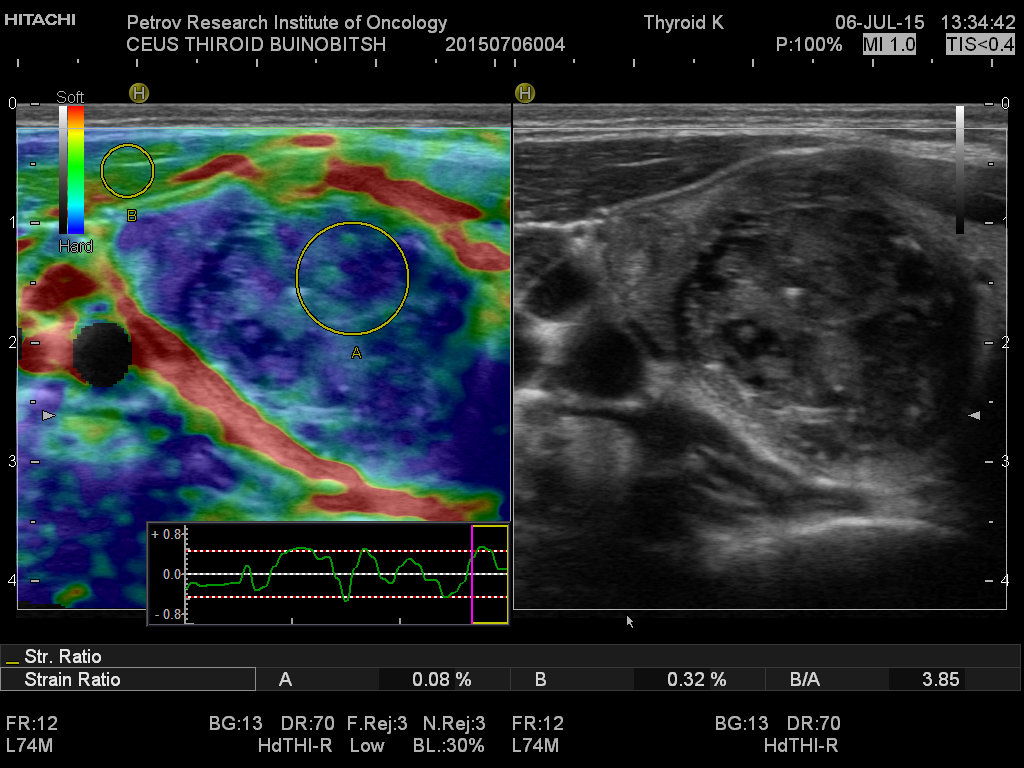

Ультразвуковая диагностика позволяет обнаружить опухолевые образования от 2-3 мм, определить точное топографическое расположение в железе, визуализировать инвазию капсулы, оценить размеры и состояние лимфатических узлов шеи.

Остеосцинтиргафия позволяет оценить наличие/отсутствие метастатического поражения костей скелета. Тонкоигольная аспирационная биопсия выполняется преимущественно под контролем УЗИ, позволяет прицельно получить материал для цитологического исследования, что позволяет в большинстве случаев верифицировать диагноз. ТАБ подозрительных лимфатических узлов дает возможность установить метастатический характер поражения.